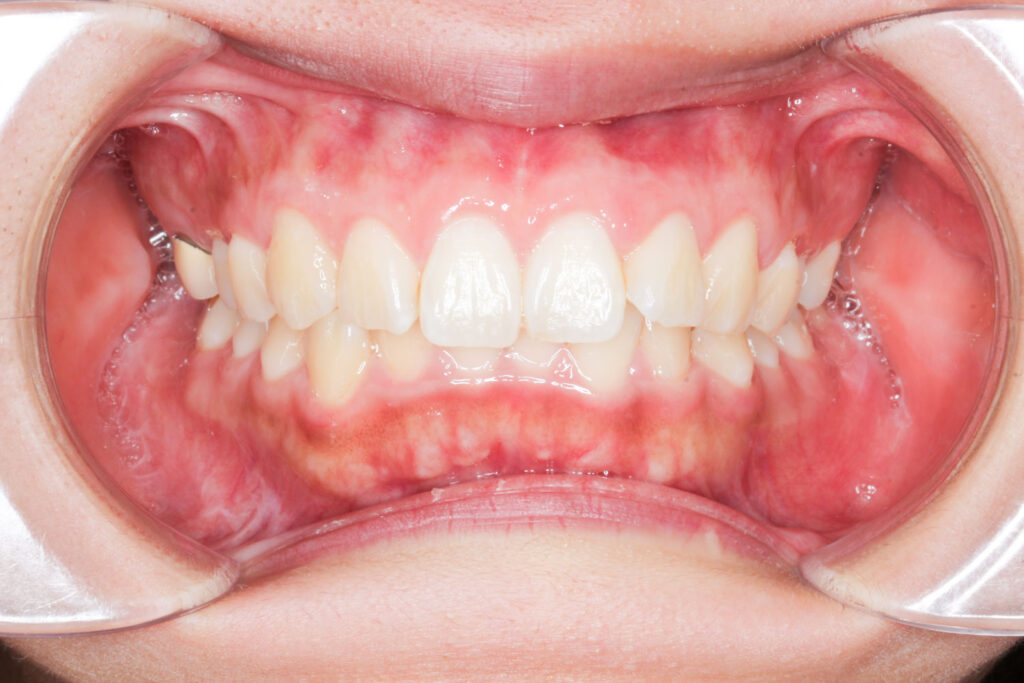

After

Before

年齢 10代

治療装置 表側の矯正装置(ホワイトコース)

治療内容 上下左右4本抜歯

治療期間 2年1か月

リスク 歯の移動に伴う痛み、歯肉退縮、歯根吸収、歯肉炎、虫歯

主訴 ガタガタが気になる

症状 叢生(ガタガタ)

治療回数 25回程度

総額費用 105万円程度